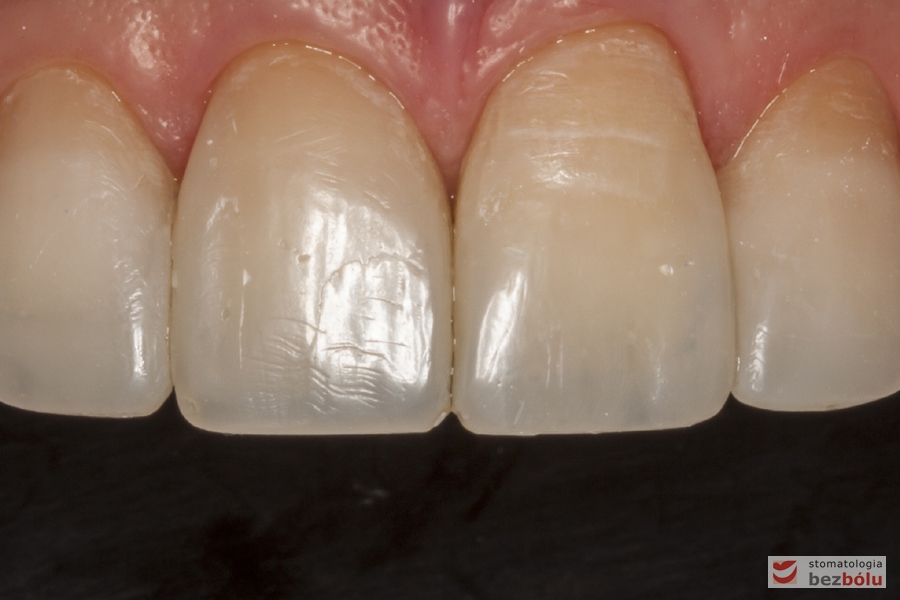

Zęby przednie w szczęce - bezpreparacyjna addycyjna rekonstrukcja materiałem kompozytowym

Zęby przednie w szczęce – bezpreparacyjna addycyjna rekonstrukcja materiałem kompozytowym